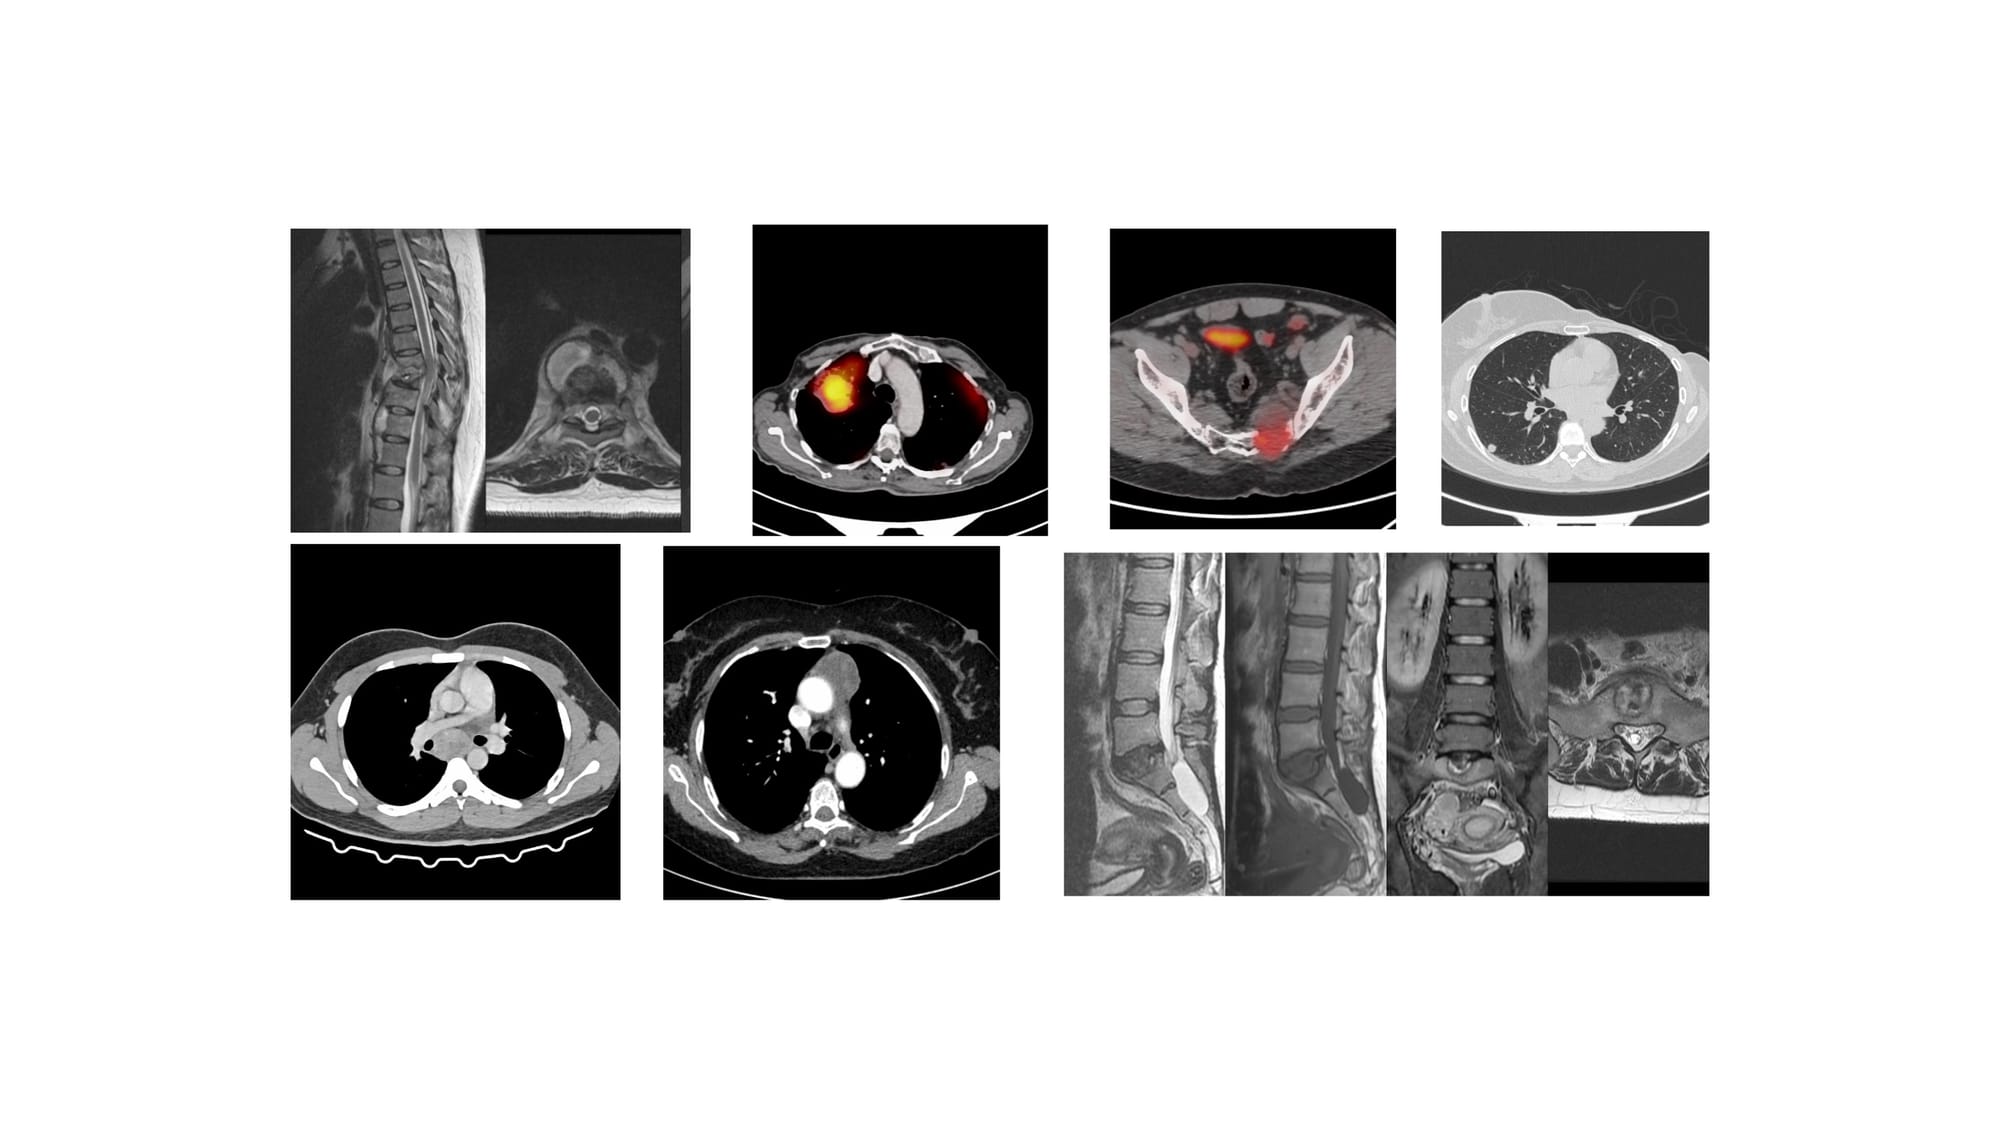

The 7 Cases for YouTube Live on 08 Jan at 7 PM Indian Standard Time

Bhavin Jankharia - 04 January 2026

Lecture - CT Guided Spine Biopsies

Bhavin Jankharia - 11 October 2025

Lecture - Pulmonary Interventions

Bhavin Jankharia - 21 September 2025